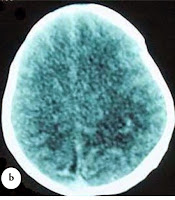

Complete blood count, prothrombin time, and partial prothrombin time were normal for age. The CT brain was obtained and showed skull depression of the left parietal area (Figure 2).

On the second day after birth, he was in good condition, good oxygen saturation in room air, feeding was started and well tolerated. The vital signs were stable. On day 3, repeat CT scan showed corrected depressed fracture

(Figures 3)

| Fig 3 Repeat CT scan head post skull elevation by Vacuum. |